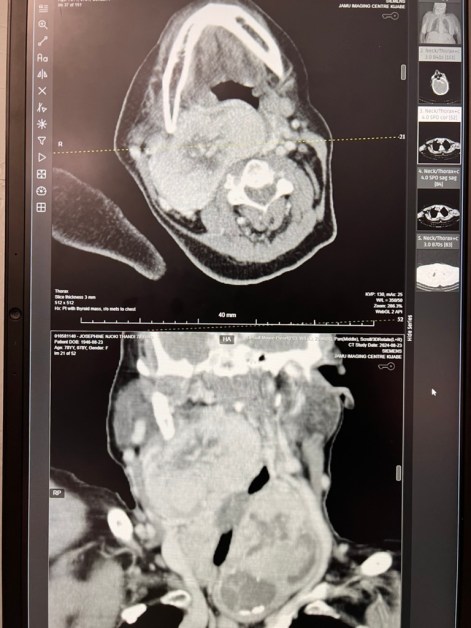

Giving Hope Through Jaw Reconstruction: Treating Ameloblastoma in Kenya

Ameloblastomas are benign but locally aggressive tumors that most often arise in the mandible (lower jaw). While they grow slowly, patients in Kenya frequently present with very large masses by the time they come for treatment — far larger than any I encountered during my surgical training in the United States. Once these tumors reach…